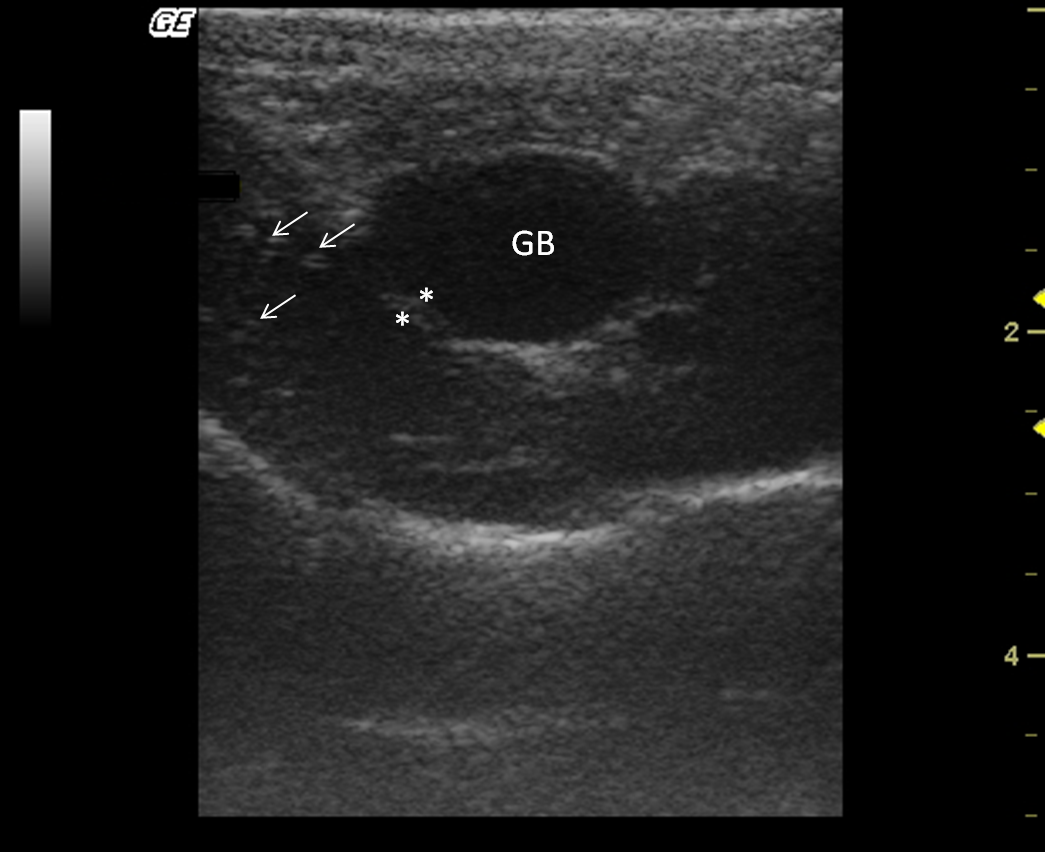

Liver and gallbladder

The liver size was assessed subjectively; it was located entirely within the rib cage, cranial to the stomach in all monkeys. All howler monkeys had liver parenchyma with homogeneous hypoechogenic echotexture compared with the cortex of the right kidney. Liver parenchyma also showed hyperechoic portal vessels walls (Fig. 4). The presence of gas in the stomach made it difficult to visualize the liver completely in two males.

Figure 4.

Transverse sonogram of the liver in an Alouatta fusca. The liver parenchyma presents a hypoechogenic ecotexture with hyperechogenic portal vessels walls, with the appearance of a “starry sky”. The gallbladder is filled with a homogeneous anechoic content, has a hyperechoic wall when compared with the hepatic parenchyma.

The gallbladder had homogeneous anechoic fluid content; luminal debris was not detected. The gallbladder wall was totally or partially visualized as a hyperechoic line when compared with the hepatic parenchyma, average measuring 1.5 mm thick. Post-mortem studies allowed identification of liver lobes: papillary process of the caudate lobe, caudate process of the caudate lobe, left lobe, quadrate lobe and right lobe; this allowed for a comparison of ultrasound imaging and anatomic position (Fig. 5).

Figure 5.

Post-mortem preparation of Alouatta fusca liver (anterior view), showing the disposition of the gallbladder (GB) and hepatic lobes: (1a) papillary process of the caudate lobe, (1b) caudate process of the caudate lobe, (2) left lobe, (3) quadrate lobe, (4) right lobe.